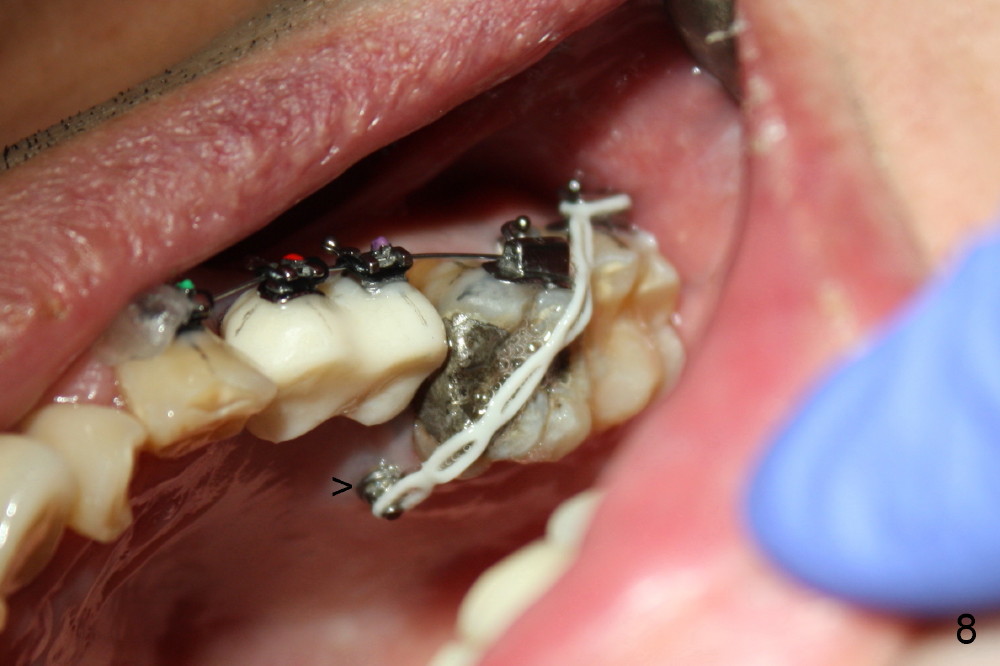

A 51-year-old man needs implants at the sites of #12,13,19 (Fig.1). The teeth #12 and 13 are extracted. An implant is placed at #19 (Fig.2 <). After osteointegration, an abutment is placed (Fig.2 A). The opposing tooth, #14, is found supraerupted. Two mini-implants are placed at the mesiobuccal and distolingual areas of #14 (Fig.3 (mirror view) <) and a power chain (*) is placed for intrusion. In the next 8 months, these 2 mini-implants become loose. Two new mini-implants are placed in the mesiolingual and distobuccal regions (Fig.4 ^). The one in the distobuccal region is loose after a while (Fig.6,7 >). In brief, mini-implants are not efficient in intrusion. At this time, the implants at the sites of #12,13 apparently osteointegrate (3 months post placement) and abutments are placed (Fig.4). Provisional crowns are fabricated (Fig.5). Brackets are placed between #11 and 15 with the bracket at #14 placed more coronally than those of the neighboring teeth (Fig.6-8). Mesially there are two excellent anchorages (#12,13) as well as the mesiolingual mini-implant. The distal anchorage is #15. In the next 5.5 months, the tooth #14 is intruded (Fig.9,10), but the 2nd molar is mobile (not as strong as #14). A longer mini-implant is placed in the distobuccal corner (>, more apical than before (Fig.7)). The distobuccal mini-implant is found to be mobile in 3 weeks (Fig.11). It appears that there is enough clearance for restoration of #19 (Fig.12). Power chains are placed between the mesiolingual mini-implant and #14 buccal tube until the appointment for crown prep. In this way, the lingual cusps may ascend (Fig.13 red arrow), while the buccal ones may descend (black arrow). The occlusal clearance will be more favorable.